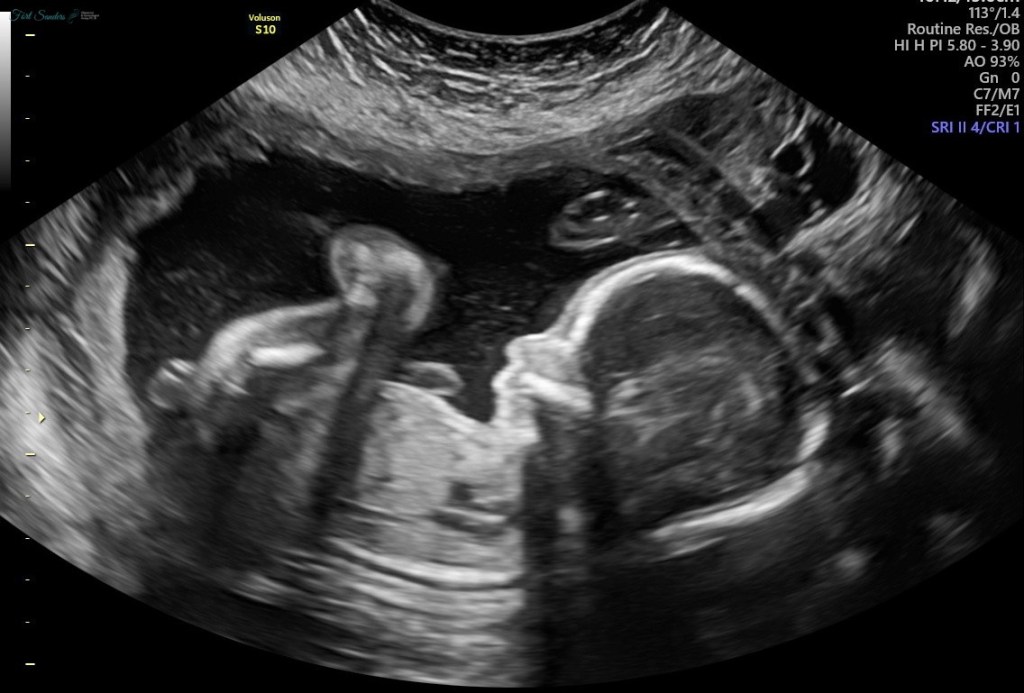

Jake and I wanted to find out about the baby’s gender in the ultrasound room as a couple. There’s something special about finding out as you’re looking right at your baby – and we wanted to have that special moment.

When the ultrasound technician told us, “it’s a boy,” that morning, I laughed and Jake said “oh my gosh, really?!”

On the frame, I dry-brush painted it gray and used the q-tips to make both pink and blue dots. I printed a copy of an ultrasound photo and put it in the photo opening.